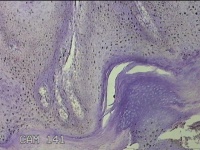

后颈部皮肤结节

性别

男

年龄

45岁

临床诊断

皮肤结节病

一般病史

发现后颈部皮肤结节半年余。

标本名称

大体所见

灰白粉红色组织1.7x0.9x0.3cm一块,表面带梭形皮肤1.7x0.9cm,皮下见结节1.5x1.1cm一个,切开结节呈实性,切面灰白粉红色,质软。